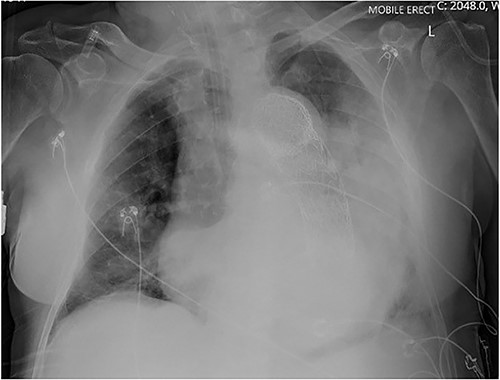

An 84-year-old male was admitted with sigmoid diverticulitis with a contained perforation in the colonic mesentery. His medical background included open thoracoabdominal aortic aneurysm repair 15 years prior, and chronic obstructive pulmonary disease. He was managed nonoperatively with intravenous antibiotics. On day 5 of admission, he acutely deteriorated with hypotension, tachypnoea and 200 mL of fresh haematemesis. Chest X-ray indicated opacification of the left lung, presumed to represent aspiration of haematemesis (Fig. 1). The patient received blood transfusion and proceeded to urgent gastroscopy, which identified old blood in the stomach and a Dieulafoy lesion, which was clipped. Post-procedure, the patient remained haemodynamically normal in intensive care, however had worsening opacification of his left lung on X-ray. The patient underwent bronchoscopy, with extraction of a further 200 mL of clot from the bronchial tree. In light of his vascular history, the patient proceeded to computed tomography (CT) angiography, which indicated a large Type 1 endoleak at the inferior margin of his thoracic aortic endograft, with a large left haemothorax and complete collapse of the left lung (Fig. 2). In the context of his comorbidities with active deterioration, the patient was palliated.

Erect AP chest X-ray indicating opacification of the left mid and lower zones, with thoracic vascular graft in situ.